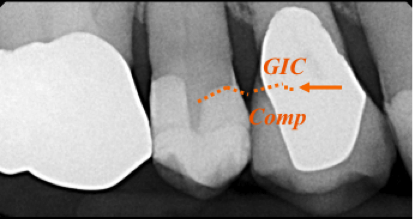

For more deeply excavated lesions whose dentin will have more tubules exposed and less peritubular dentin to which to bond, glass-ionomer cement forms a “chemically fused seal,” and its high fluoride release and internal remineralization help to prevent future decay. Therefore, this material can serve well as a base or liner in deeply excavated lesions (Figure 6).11-15

In the case of a patient requiring a Class II cavity preparation whose margins may be on root surface, glass-ionomer cement can be placed as a liner or base followed by a “composite cap” to complete the restoration (Figure 7). For the “open sandwich” technique, the glass-ionomer cement base extends to the internal surface of the matrix and will be in contact with the intracrevicular environment for purposes of ion exchange.11,16

Figure 6. Glass-ionomer cement used as a base or liner prior to composite placement in deeply excavated lesions.

Figure 6

Figure 7. “Open sandwich technique” in which glass-ionomer cement is placed after tooth conditioner and thorough rinse.

Figure 7